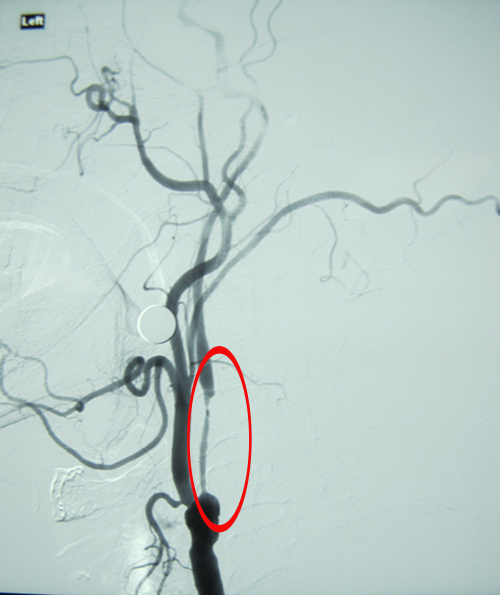

DSA:双侧颈内动脉起始部、左颈总动脉膨大处、左侧颈内动脉虹吸段及左侧大脑中动脉多发动脉粥样硬化斑块;左侧颈内动脉起始段管腔重度狭窄。

左侧颈内动脉线样狭窄